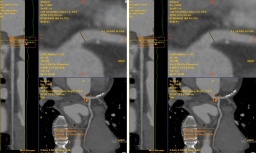

Bệnh nhân nhập viện trong tình trạng khó thở, tức ngực và ho kéo dài. Kết quả chụp CT cho thấy khối u phổi kích thước khoảng 3 cm, nằm ở thùy trên phổi trái, vị trí sát động mạch chủ và tĩnh mạch phổi là “vùng nguy hiểm” trong phẫu thuật lồng ngực.

Theo PGS-TS.Vũ Hữu Vĩnh, Giám đốc Trung tâm Ngoại Lồng ngực - Mạch máu, nếu áp dụng phương pháp mổ mở truyền thống, người bệnh sẽ phải đối mặt với mức độ xâm lấn lớn và nguy cơ biến chứng cao. Trong khi đó, phẫu thuật nội soi thông thường gặp nhiều hạn chế trong không gian hẹp, khó thao tác chính xác, tiềm ẩn nguy cơ tổn thương mạch máu lớn gây xuất huyết ồ ạt.

Trước những thách thức này, ê-kíp phẫu thuật đã lựa chọn phương án sử dụng robot Da Vinci Xi, kết hợp kỹ thuật sinh thiết lạnh để vừa đánh giá bản chất khối u, vừa thực hiện phẫu thuật triệt căn trong cùng một cuộc mổ.

Trong suốt quá trình mổ, robot Da Vinci Xi cho phép phẫu thuật viên điều khiển các cánh tay robot xoay linh hoạt 540 độ như cổ tay người, kết hợp hệ thống camera 3D phóng đại 10-15 lần, giúp quan sát rõ ràng và thao tác chính xác tại những vị trí hiểm hóc mà kỹ thuật nội soi thông thường khó tiếp cận.

Do khối u nằm gần các mạch máu lớn, nguy cơ chảy máu cao, ê-kíp còn sử dụng máy cắt nối cơ học chạy điện để khâu nối mô phổi bằng các ghim titan siêu nhỏ.

Sự phối hợp giữa khả năng bóc tách tinh vi của robot và cơ chế cắt nối ổn định của thiết bị hỗ trợ giúp kiểm soát tốt tình trạng chảy máu, giảm rung chấn và hạn chế biến chứng trong suốt cuộc mổ.